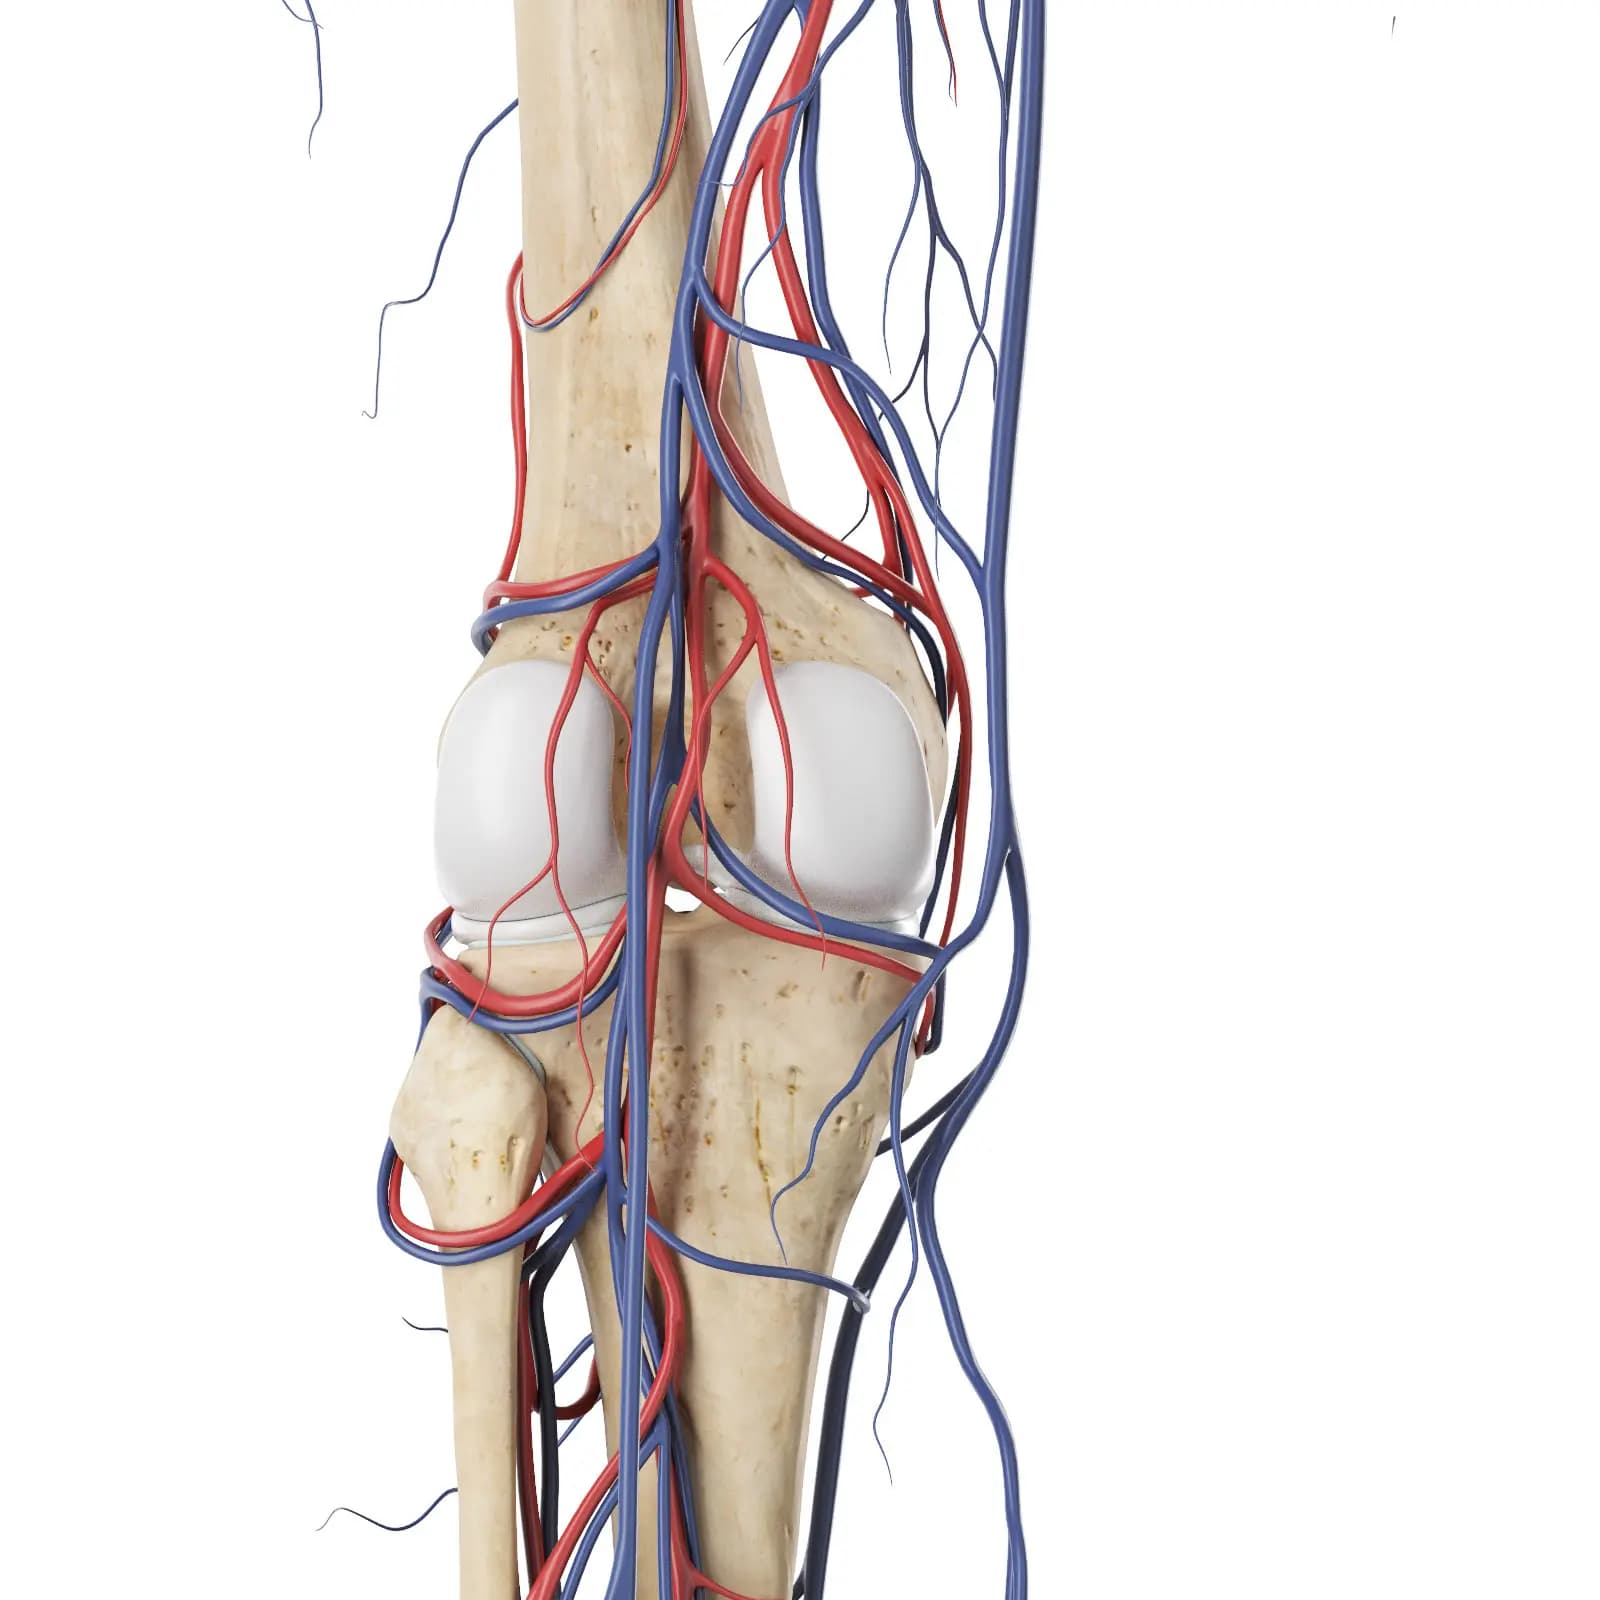

3d Rendered Medical Illustration Of The Vascular System Of The Knee

3d Rendered Medical Illustration Of The Vascular System Of The Knee